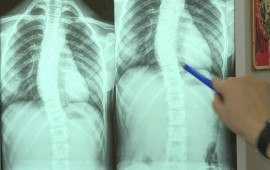

"Son zamanlar 8-12 yaş aralığındakı uşaqlarda bel və boyun ağrılar